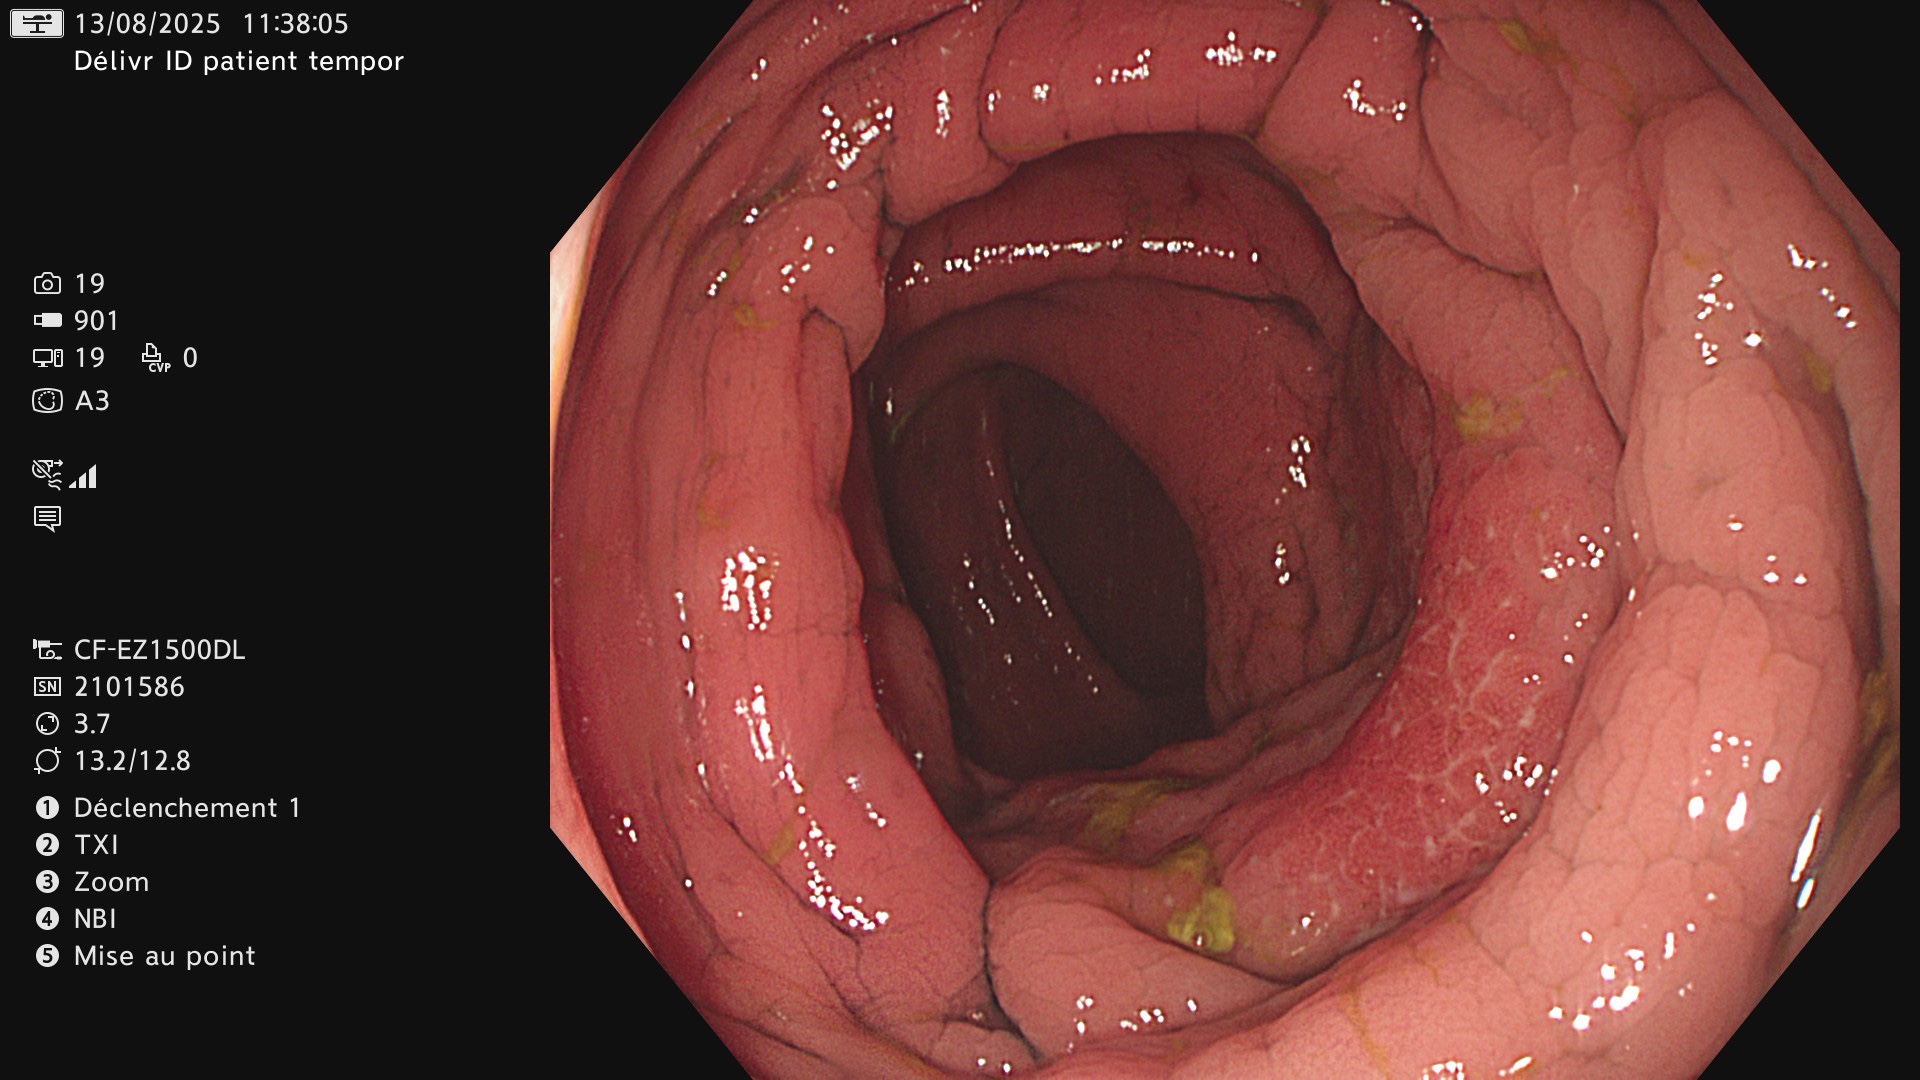

Maladie presque cicatrisée

Ci-dessous, en endoscopie on constate aussi que la maladie garde des petites plages actives sur un colon qui semble presque cicatriciel.

Même aspect en chromoendoscopie virtuelle NBI